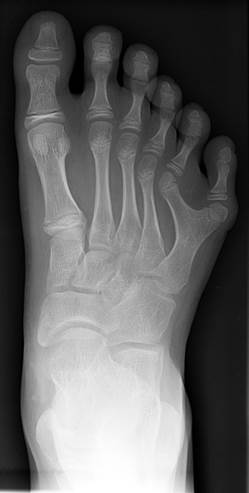

Сандалевидная щель |

полидактилия кистей |

полидактилия стоп |

стопа-качалка |